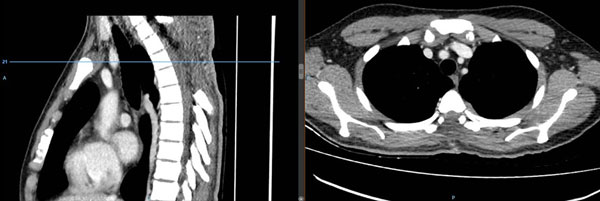

Se realizó laminectomía D2-D6 con exéresis macroscópicamente total del tumor de color amarillo pardo (Figura 2). El estudio anatomopatológico e inmunohistoquímico de la pieza operatoria fue linfohistiocitosis-enfermedad de Rosai-Dorfman. En el postoperatorio inmediato cursó con fiebre sostenida de 39°- 40° la que persistió por 3 semanas, cediendo en la cuarta semana. Se realizaron hemocultivos seriados, urocultivo, cultivo de líquido cefalorraquídeo con resultados negativos para infección. También presentó disminución de peso y dorsalgia, atribuidas a la postración. Por diagnóstico diferencial de síndrome paraneoplásico, se administró corticoterapia (prednisona 1 mg/kg) antes y después del acto quirúrgico. Posteriormente, y por sugerencia de Hematología, se agregó talidomida y dexametasona por 2 meses, además de tratamiento sintomático.

Figura 2. Tomografía computada de columna dorsal con contraste. Se evidencia laminectomía D2 – D6, no se observa lesión hipercaptadora de contraste sugerente de lesión neoproliferativa residual.